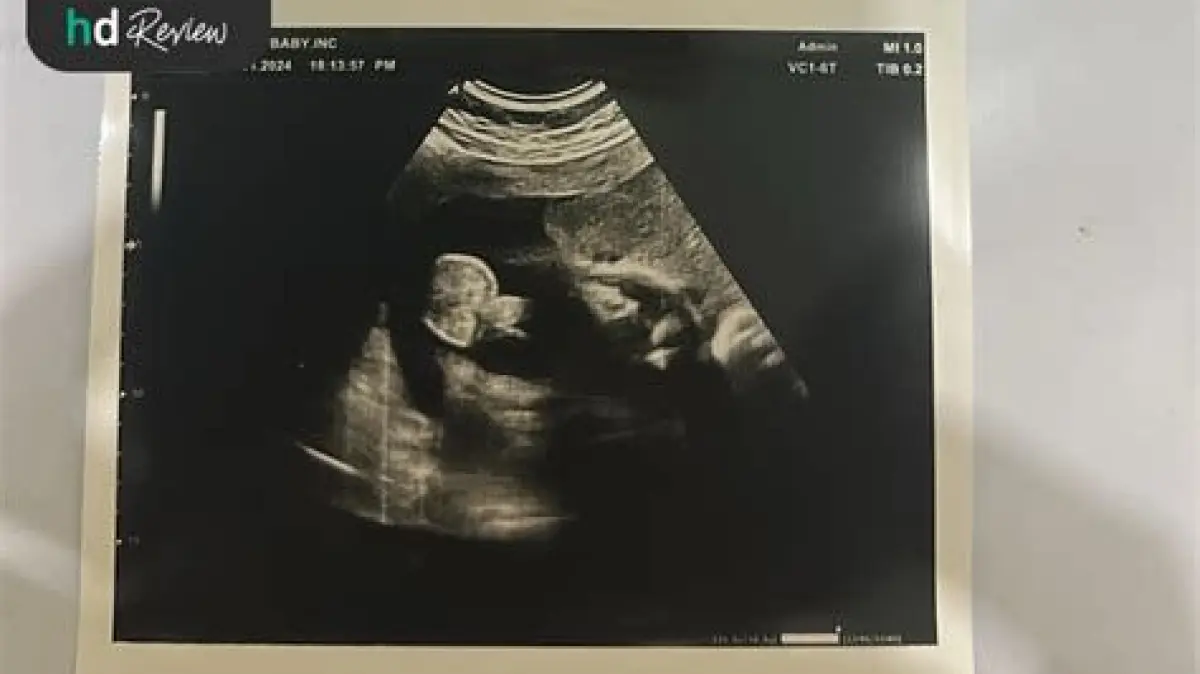

USG 2 dimensi (2D) adalah salah satu metode pencitraan medis yang umum digunakan selama kehamilan. Banyak calon orang tua bertanya-tanya, seberapa akuratkah USG 2D dalam memberikan informasi tentang perkembangan janin? Di tengah perkembangan teknologi USG yang semakin canggih, penting untuk memahami apa yang bisa dan tidak bisa diandalkan dari pemeriksaan USG 2D ini. Kami akan membahas secara mendalam mengenai akurasi USG 2D, faktor-faktor yang mempengaruhinya, serta kapan sebaiknya mempertimbangkan jenis USG lainnya.

USG 2D mampu memberikan gambaran dua dimensi dari janin, memungkinkan dokter untuk mengamati struktur anatomi dan organ-organ penting. Akurasinya bervariasi tergantung pada beberapa faktor: